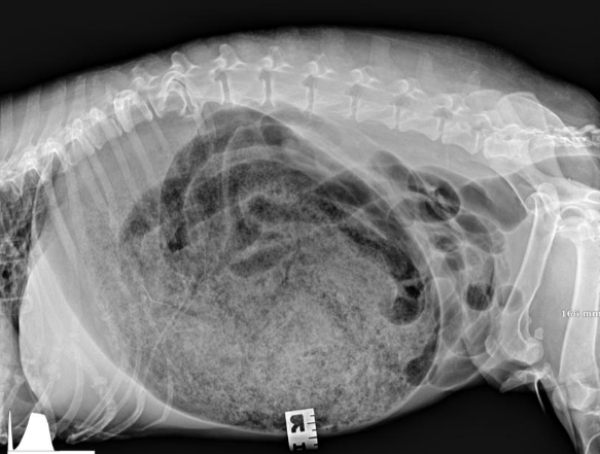

Radiographs were taken before treatment and showed a very distended stomach consistent with reported history. The owner consented to treatment with gastric lavage after discussion of the efficacy of emesis in this case.

Treatment was initiated, and after intubation, a tube was placed down to her stomach and cold water was pumped in to help remove dough pieces. This was successful in her case and was repeated on both right and left lateral sides twice to increase likelihood of removal of all the dough. She recovered well but was kept on fluids, anti-nausea and pain meds due to clinical signs. Repeat x-rays were taken to make sure the residual dough in the GI tract remained non obstructive. Before and after radiographs were sent to specialists to confirm removal of dough.